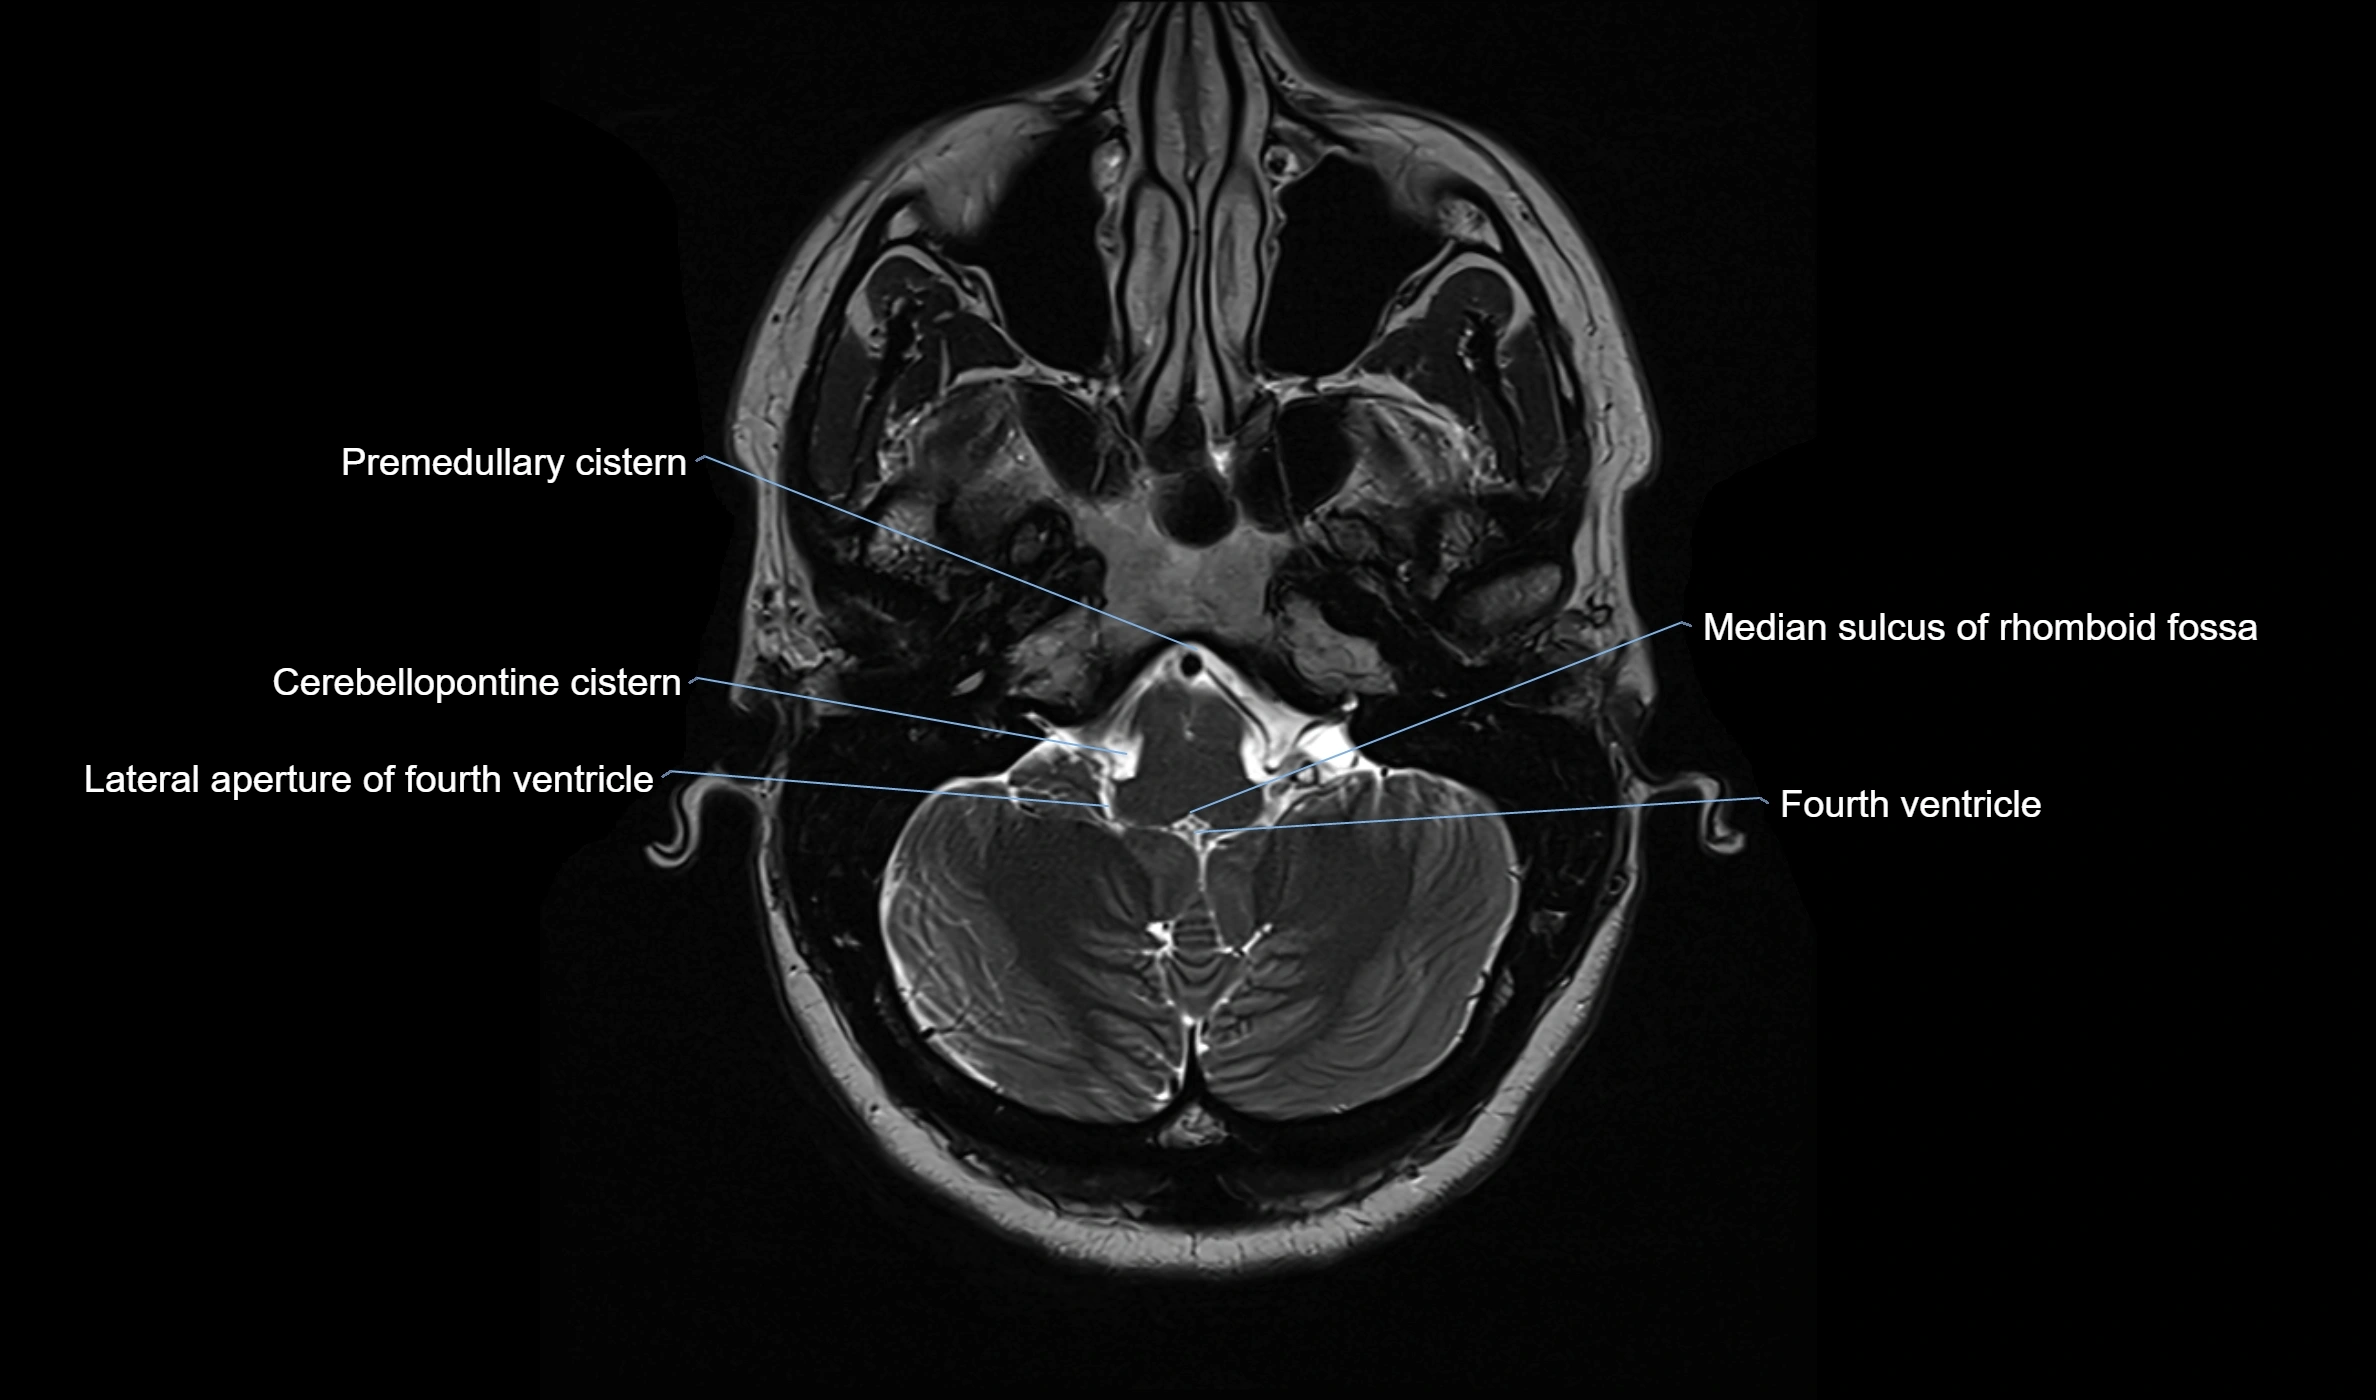

CT image

image